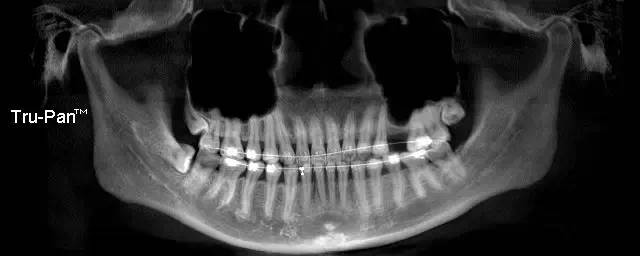

第一圖、臨床上最常見的上頜竇類型之一(高度稍顯不足、上頜竇內(nèi)干凈,提示做上頜竇內(nèi)提升即可)